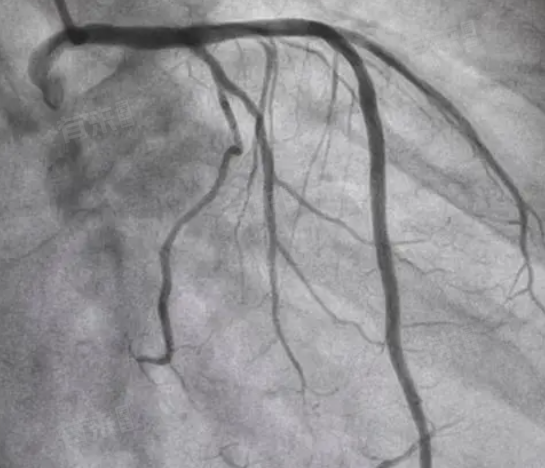

1、检查方式差异:心脏造影主要包括冠状动脉CT和经皮冠状动脉造影两种。冠状动脉CT作为无创性检查,费用相对较低,一般在1000元左右,适用于初步筛查或轻度冠状动脉狭窄患者。而经皮冠状动脉造影,需通过导管插入主动脉并注入造影剂,属于微创检查,费用较高,一般在4000-5000元之间,能更直观地显示冠状动脉的形态及病变情况,适用于中重度冠状动脉狭窄或疑似冠心病的诊断。